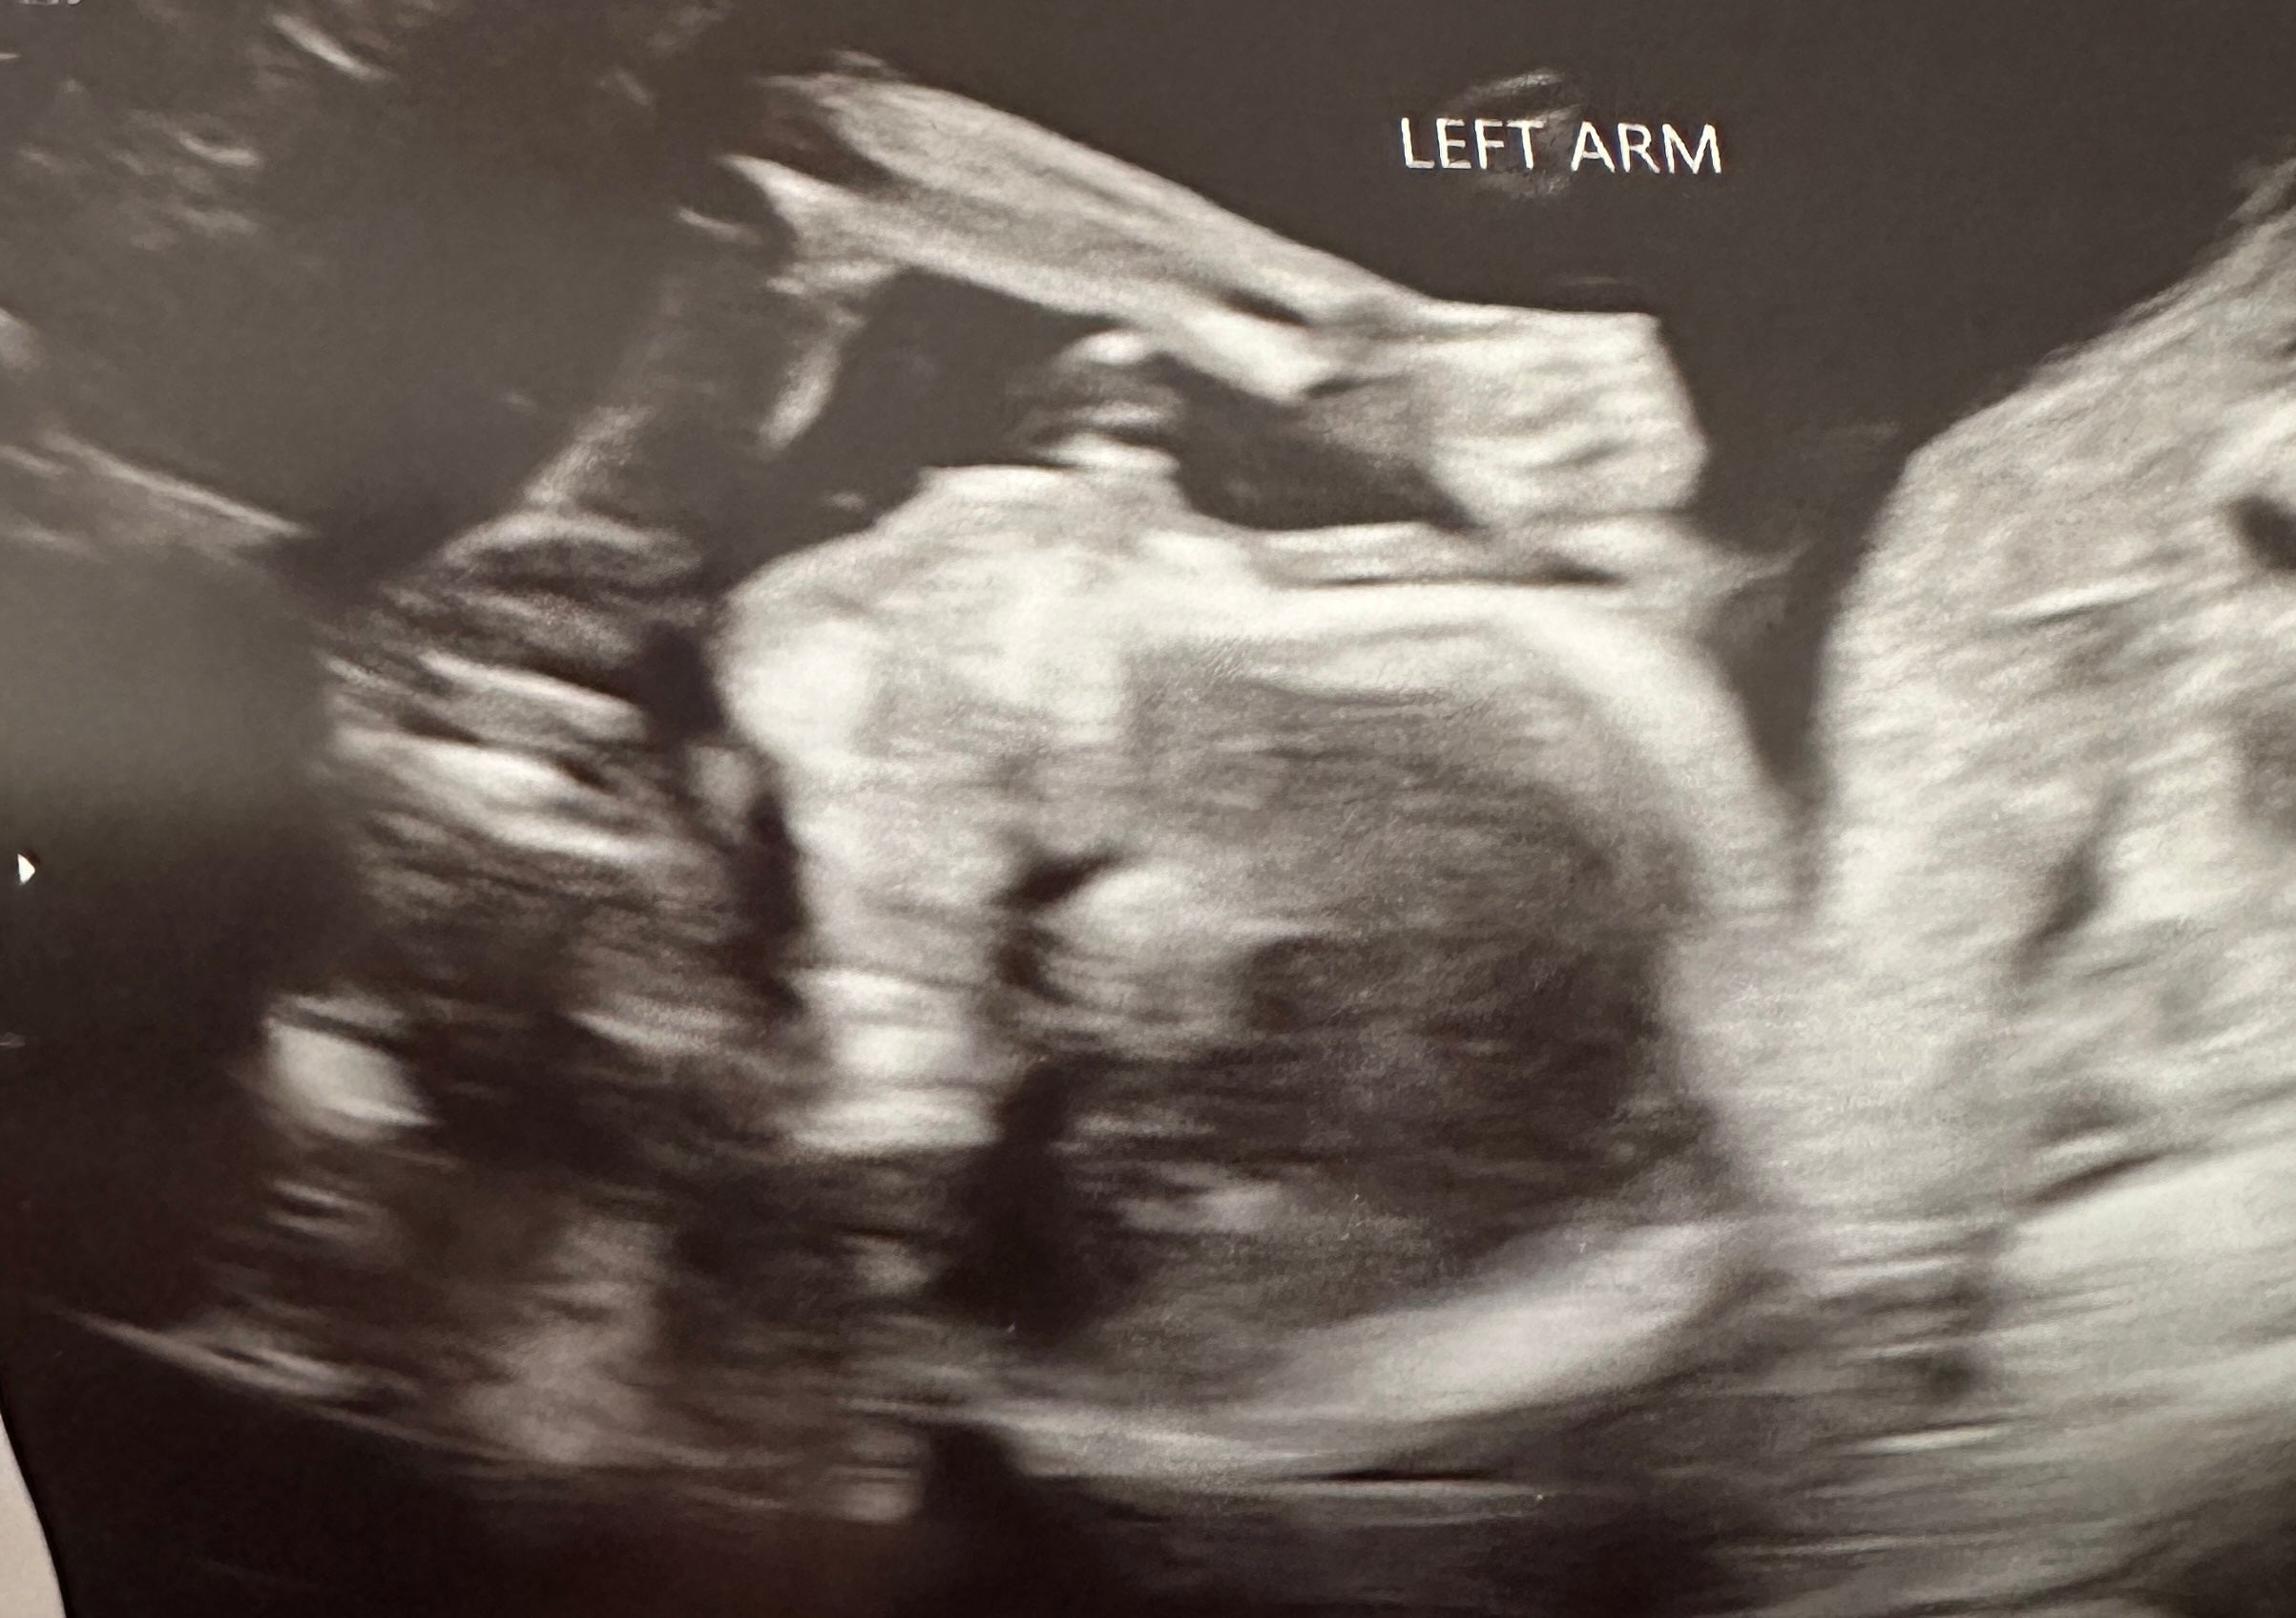

My husband and I were trying for one year to get pregnant. We finally conceived but we lost her in the second trimester. We wanted to try again as soon as the doctors gave us the green light but I was dreading the whole process again. Trying to conceive is so exhausting and mentally draining. I saw a Tiktok (I can’t remember the creator) talking about Mosie and how it worked for them. I figured what’s there to lose? We used ovulation strips to monitor my LH surge and once I got a positive we used one of the two syringes the kit comes with. I was saving the second for another month if the first time didn’t work. Well, the first time worked and we got a positive pregnancy test a couple of weeks later! I’m currently 19 weeks pregnant with our rainbow baby! We only had to try one month!